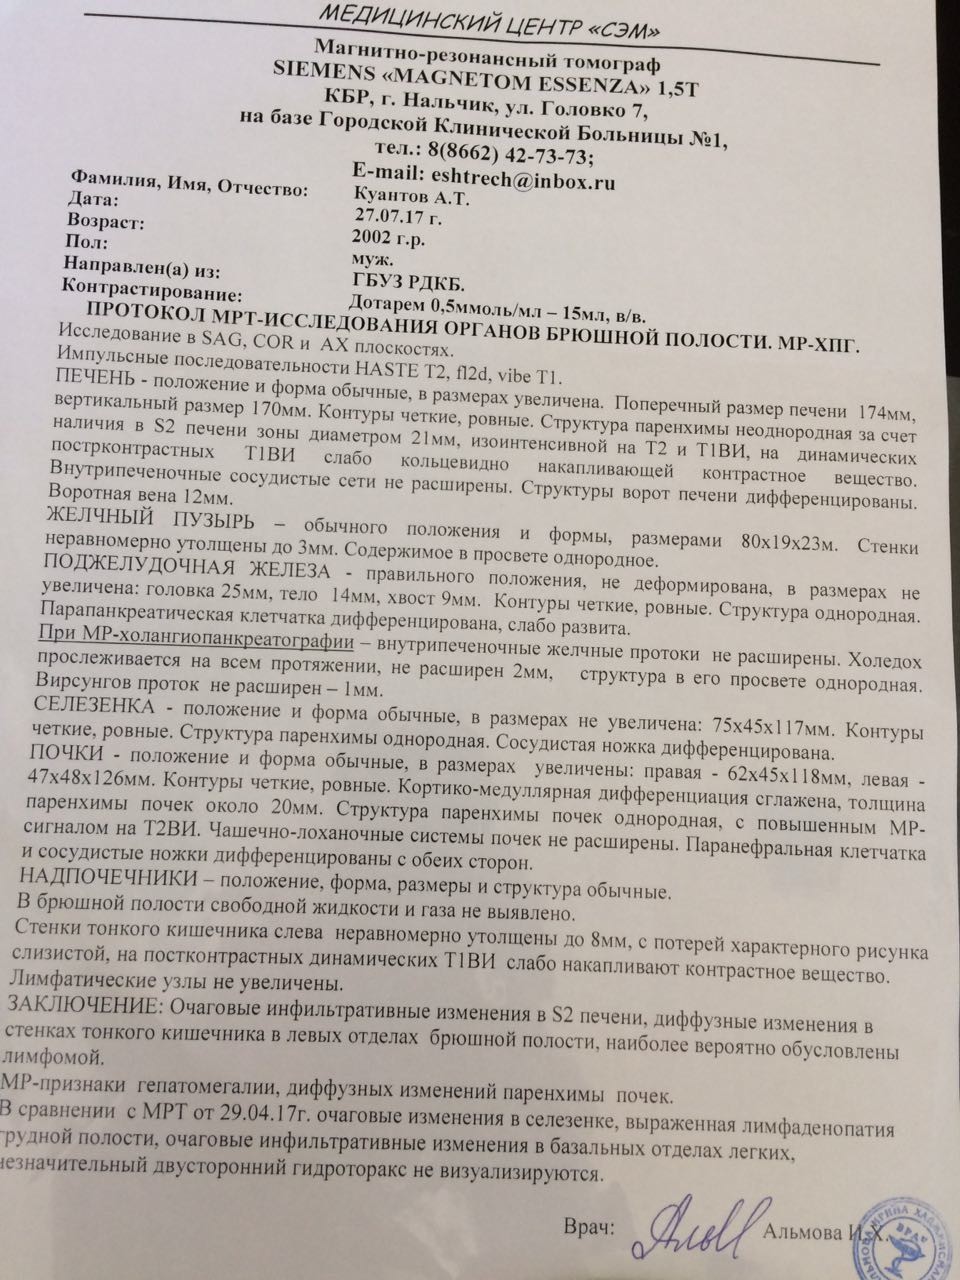

Диагностика лимфомы Ходжкина с помощью ПЭТ и КТ

Раздел: Светлые идеи